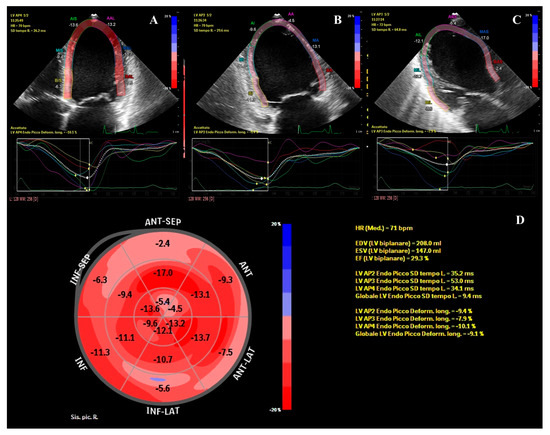

A Young Patient Presenting with Dilated Cardiomyopathy and Renal Infarction during Treatment with Isotretinoin: Mere Coincidence or Serious Side Effect of a Drug Commonly Used in Adolescence?

Isotretinoin or 13-cis-retinoic acid (RA) is one of the most effective and widely used drugs for the treatment of severe acne vulgaris. Despite being deemed safe, no definite consensus has been reached on the cardiovascular risk of RA derivatives. We report a case [...] Read more.

Isotretinoin or 13-cis-retinoic acid (RA) is one of the most effective and widely used drugs for the treatment of severe acne vulgaris. Despite being deemed safe, no definite consensus has been reached on the cardiovascular risk of RA derivatives. We report a case of heart failure due to dilated cardiomyopathy (DCM) and concomitant renal infarction occurring after 5 months of isotretinoin use in a previously healthy 18-year-old male. The patient, with a history of acne vulgaris, presented to our emergency department with left iliac fossa pain and effort dyspnea. A trans-thoracic echocardiogram showed DCM and severely reduced left ventricle ejection fraction (LVEF: 29%). During hospitalization, a total body computed tomography (CT) showed an ischemic lesion in the left kidney. Ischemic, autoimmune, infective, and heritable causes of DCM were ruled out. Cardiac magnetic resonance (CMR) evidenced LV circumferential mid-wall late gadolinium enhancement. Heart failure therapy was promptly started and up-titrated, but only poor LVEF improvement was detected overtime. Our case aims to raise awareness on rare life-threatening cardiovascular events possibly associated with isotretinoin use. To the best of our knowledge, this is the first described case of renal thromboembolism and severe DCM leading to implantable cardioverter-defibrillator (ICD) implantation occurring during isotretinoin treatment. Full article